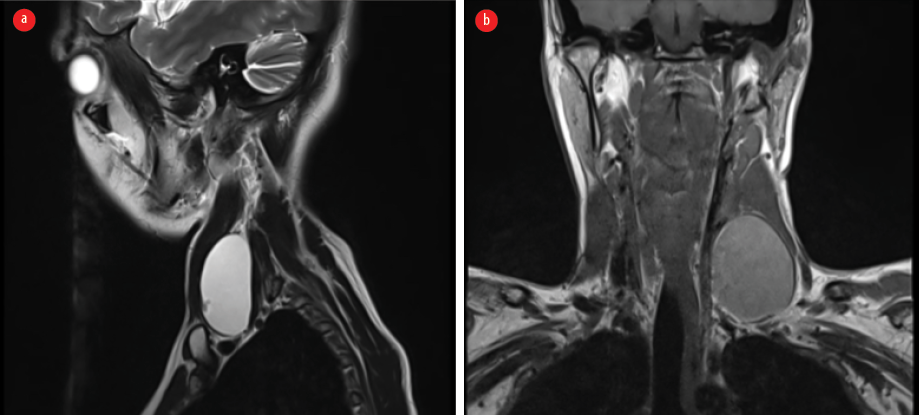

A 25-year-old female presented with a three-month history of swelling and pain in the left lateral neck, exacerbated during eating. On examination, a 4–5 cm enlargement in the left lateral neck was observed, associated with pain on swallowing and slight mobility with tongue protrusion. No thyroid enlargement or signs of hyper or hypothyroidism were noted, and cervical lymph nodes were not palpable. Routine blood work and thyroid function tests were within normal limits. Neck ultrasound revealed a cystic lesion (46 × 23 × 18 mm) in the anterior lateral neck, with the thyroid appearing normal. A radiological diagnosis of a branchial cyst was initially suggested, and further confirmation through histopathology and cytology correlation was advised. Subsequent magnetic resonance imaging confirmed the findings [Figure 1].

Figure 1: (a) MRI showing a heterogeneous swelling in the midline of the neck, and (b) in the left lateral part of the neck.